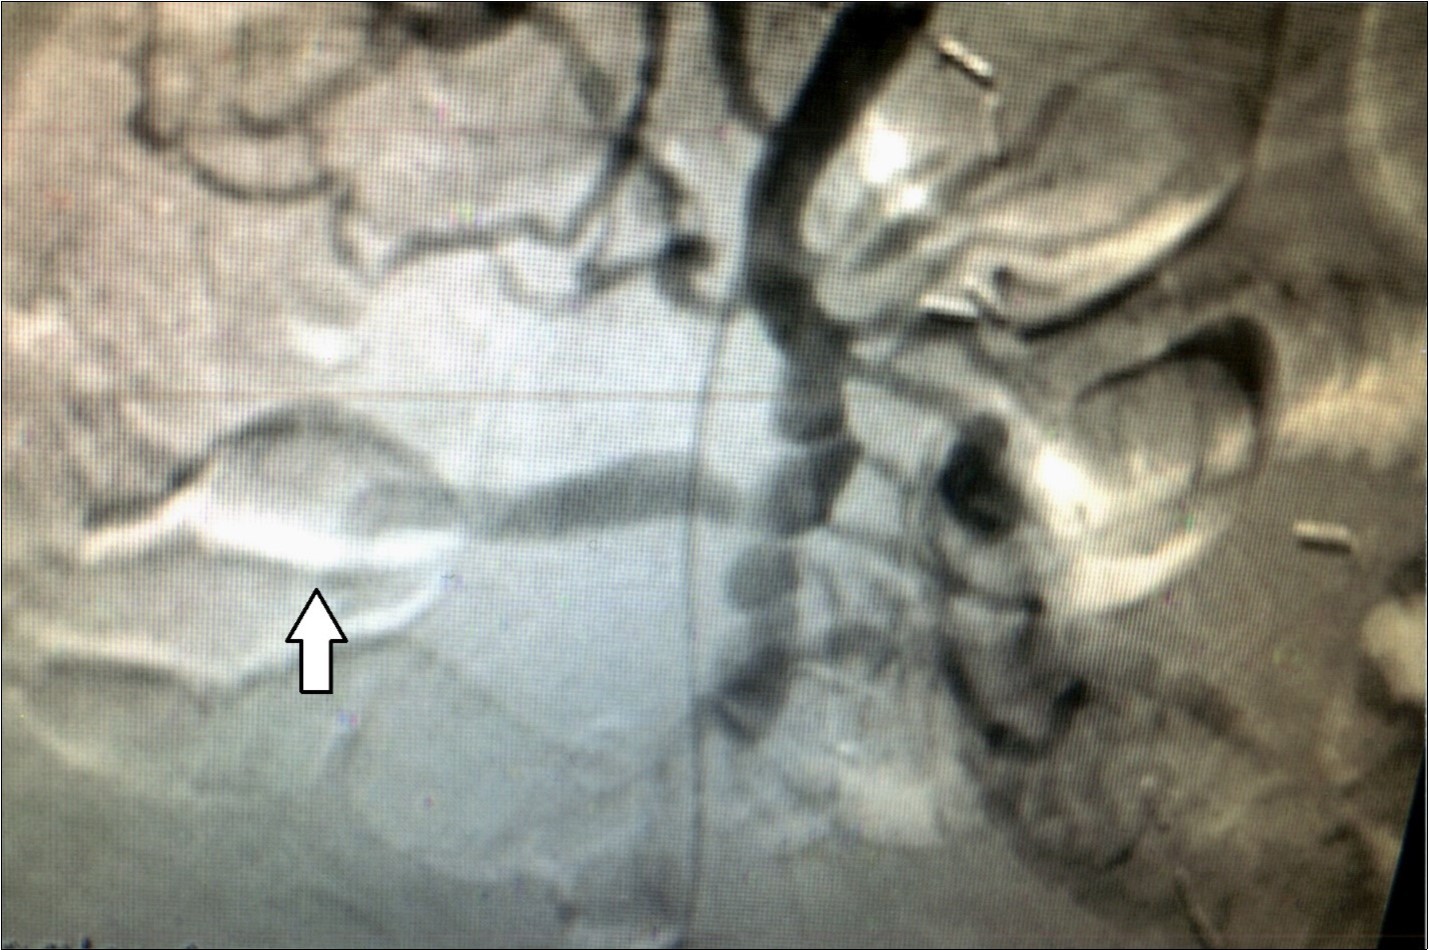

A 50 year old immune compromised patient was admitted to Bayonne Hospital on July 15, 2018, with severe gastrointestinal bleeding and anemia requiring six units packed red cells, two units of platelets and 2 units of fresh frozen plasma. Endoscopy revealed massive upper GI bleeding from duodenal ulcer. Epinepherine injection of the ulcer did not stop the bleeding. Percutaneous arteriogram revealed an aneurysm of the right hepatic artery bleeding into the first part of the duodenum wall. It was embolized, Figure 4. Past history revealed AIDS, Syphilis and tuberculosis. He had been on ventilator which was discontinued several days later. He is still hospitalized to treat his infections and a great deal of confusion, six weeks later. He is presumed deceased.